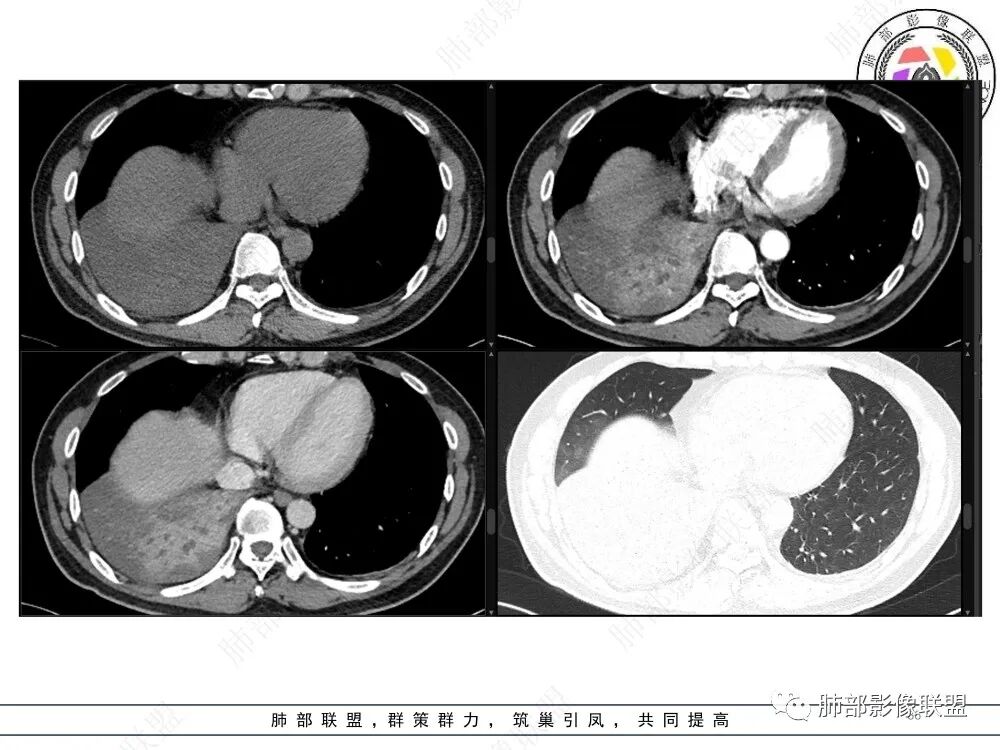

右肺下叶实变影,局部膨隆,边缘磨玻璃密度影,肺门区域明显强化考虑恶性,腺癌可能。

右肺下叶实变表现,强化和形态不考虑门口堵所致不张,枯树枝不明显,整个肺叶考虑肿瘤浸润,首先要考虑腺癌

右肺下叶实变,周围磨玻璃,近端支气管扩张,管壁凹凸不平,远端阻塞,可见粘液栓,不均匀强化,有低密度无强化影,其内血管显示尚可,考虑粘液腺癌,鉴别淋巴瘤

右肺下叶大片实变,密度不均匀,可见支气管充气征及粘液区,右肺下叶支气管内结节影,下叶支气管阻塞,病灶前下可见磨玻璃影,右侧积液,考虑粘液腺癌,鉴别类癌?

中央型肿瘤pk周围型肿瘤  。壮年男性,热咳一周伴气喘,中性白细胞升高,临床是个感染过程。支持中央型病变的证据:1  肺门明显强化结节 2 横s征  3 支气管粘液栓  4 主支气管变窄,似见冰山征      支持周围型病变:1 按叶段塑形  2 血管造影征  3 病灶内弥漫高强化  4 周围伴磨玻璃灶,但境界不清继发感染?误吸?综合 中央型肿瘤可能大:类癌》鳞癌

右肺下叶不张,右下肺门区高强化结节,似乎呈冰山征,首先考虑类癌可能

CT提示1、右肺下叶气管堵塞伴阻塞性肺不张,肺炎征象。2、破坏气管周边肿物可见结节样,肿物整体呈团块样

3、增强可见肿物明显强化。4、肿瘤内部血管可见破坏征象,但是破坏不完全。5.肿物坏死征象不明显。